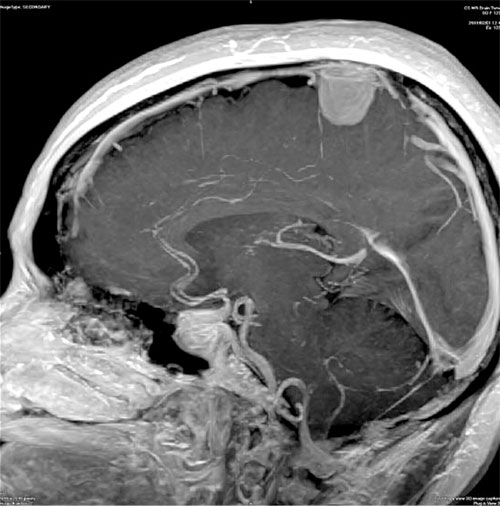

Ρίχνουν «δίχτυα» για να προλάβουν τα εγκεφαλικά επεισόδια οι επιστήμονες. Σύμφωνα με δυο νέες επιστημονικές έρευνες που επικαλείται δημοσίευμα του BBC, οι ειδικοί έχουν στα «σκαριά» ένα ειδικό «δίχτυ»- πλέγμα, το οποίο θα μπορεί να αφαιρεί εγκαίρως τους θρόμβους από τα αγγεία του εγκεφάλου, μειώνοντας σημαντικά τον κίνδυνο εγκεφαλικού αλλά και καθιστώντας τις εγχειρίσεις μετά το επεισόδιο πιο αποτελεσματικές και την ανάρρωση του ασθενούς ταχύτερη.

Εκτός των εγκεφαλικών, οι θρόμβοι στα αγγεία του εγκεφάλου αποτρέπουν την ροή οξυγόνου προς τον εγκέφαλο, κάτι που προκαλεί παράλυση και ενίοτε προβλήματα στην ομιλία και την άρθρωση του ανθρώπου.

Σύμφωνα με τις μελέτες, μέσω ενός μικρού σωλήνα, οι γιατροί θα βυθίζουν στον θόλο του εγκεφάλου του πάσχοντος κάτι σαν λεπτό καλώδιο. Αυτό θα πλέκεται σαν «δίχτυ» γύρω από το θρόμβο και θα τον αφαιρεί.

Μάλιστα, κατόπιν μελετών, προέκυψε ότι οι ασθενείς οι οποίοι θεραπεύονται από θρομβώσεις στον εγκέφαλο κατ’ αυτόν τον τρόπο έχουν διπλάσιες πιθανότητες να αποκατασταθεί πλήρως η υγεία τους και οι συνθήκες της ζωής τους μετά την επέμβαση εν συγκρίσει με ασθενείς που θεραπεύονται με άλλες μεθόδους.